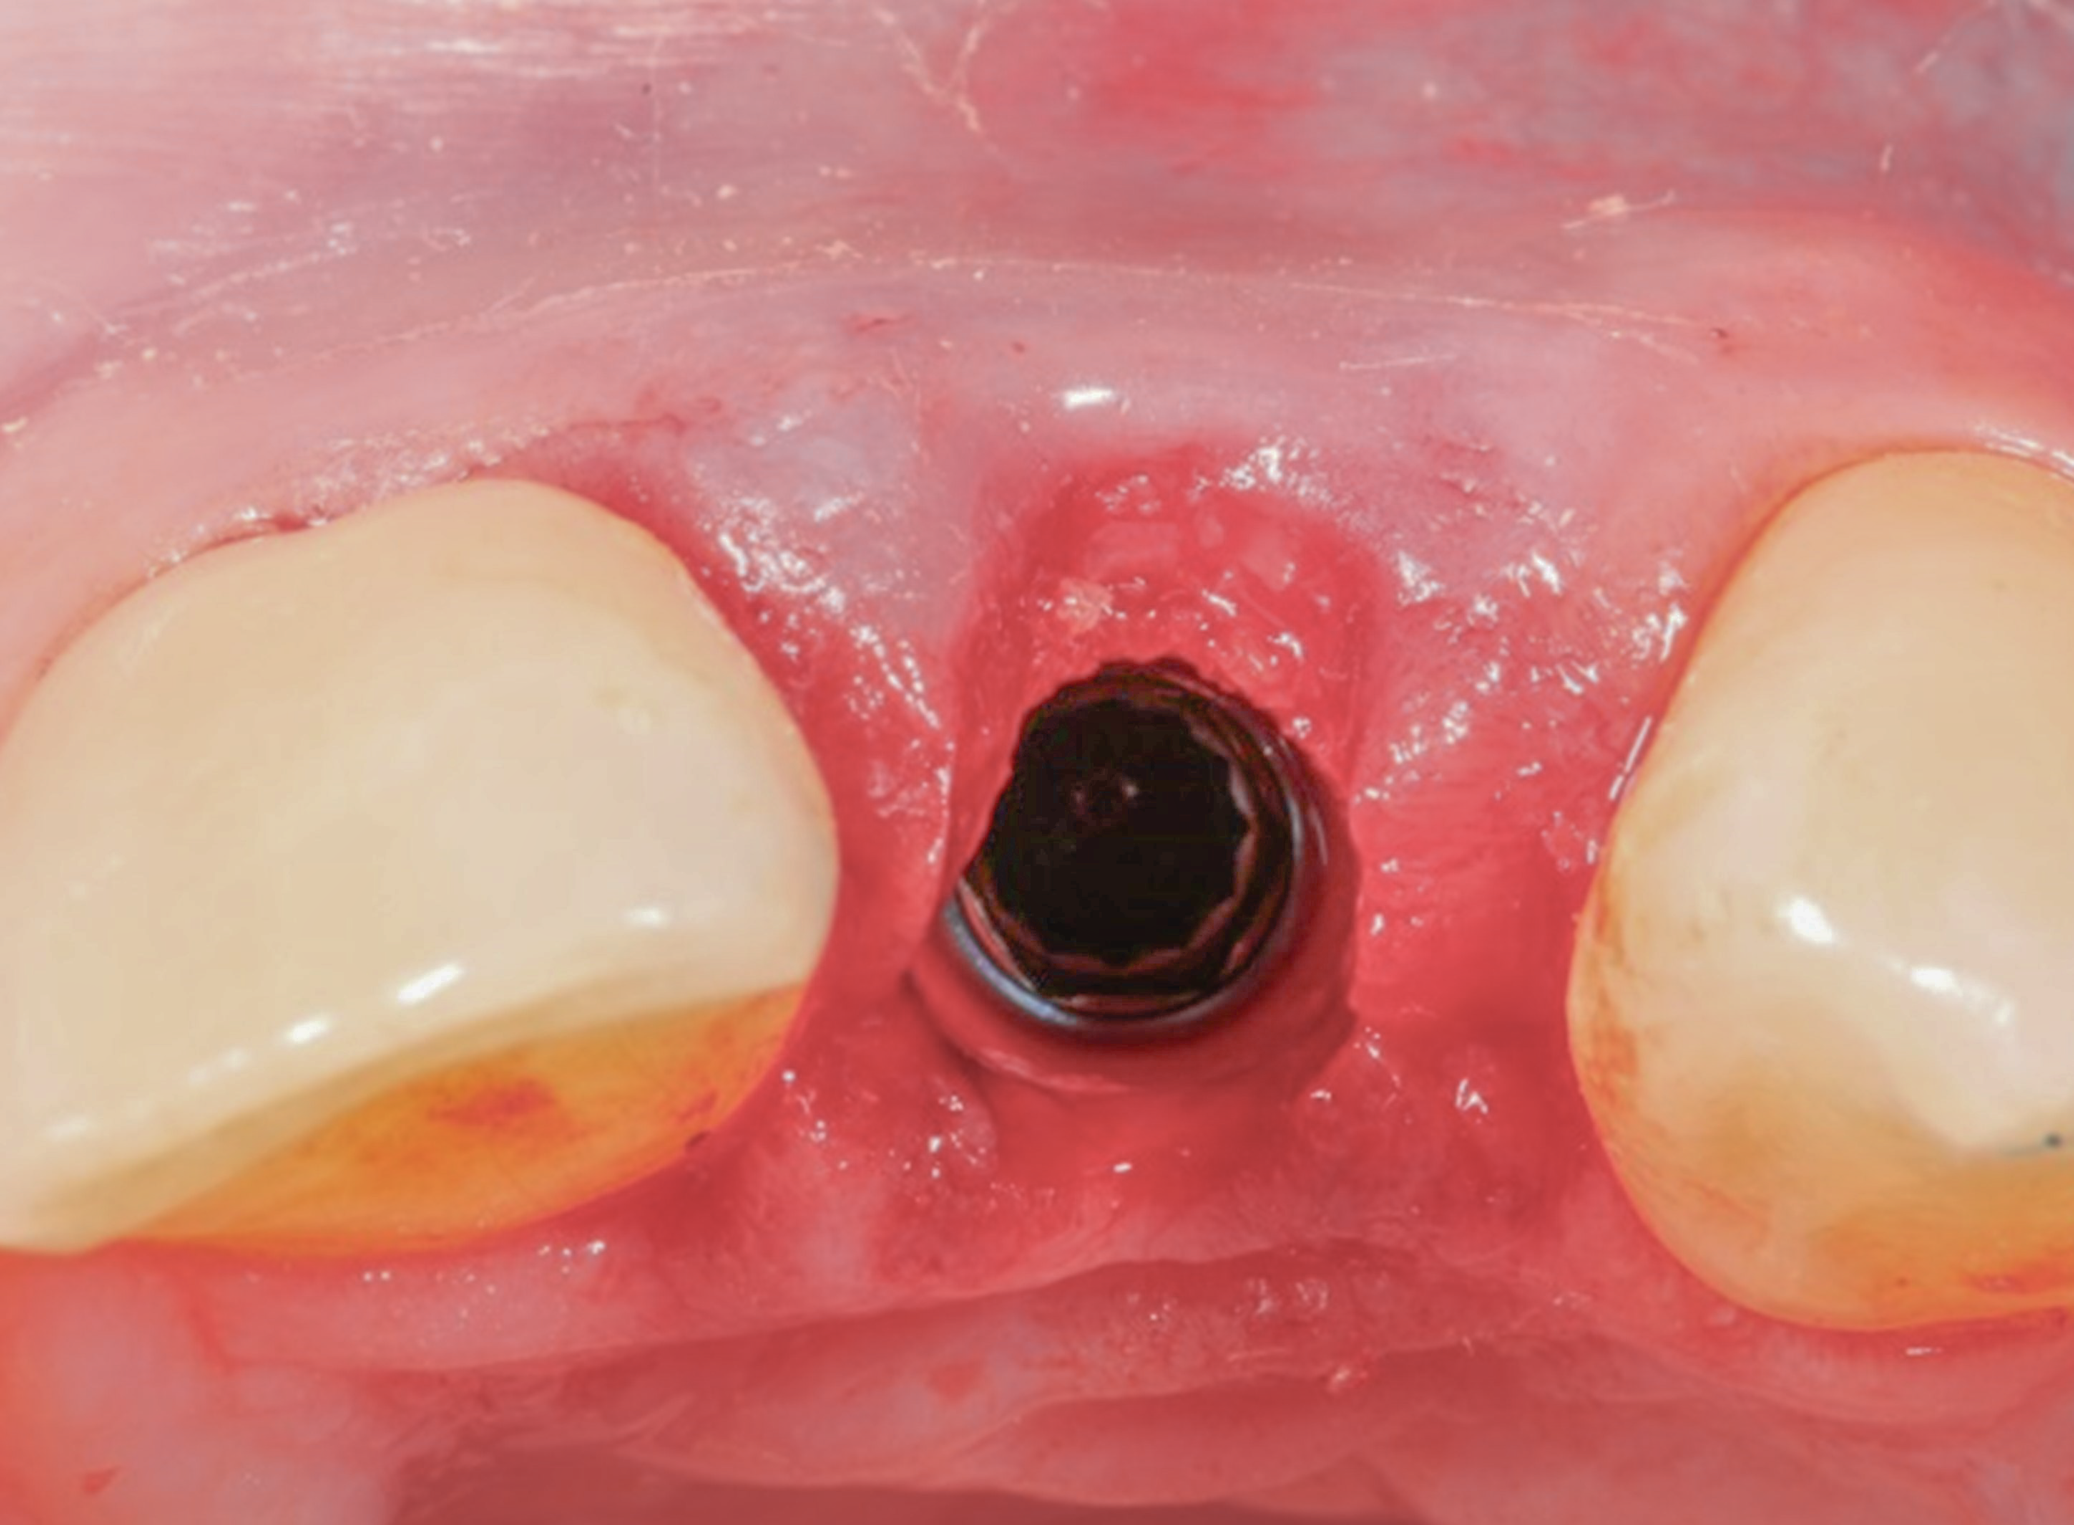

Fig 13. The healing abutment is removed.

Figure 13